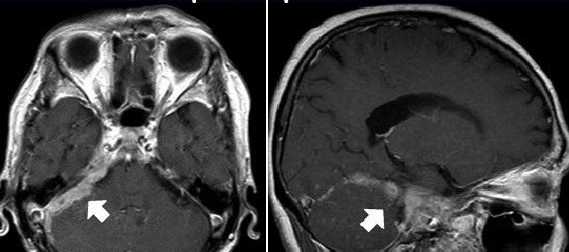

Характеризуется односторонним поражением всех черепных нервов при плоских (метастатических) опухолях в области одной половины основания черепа, чаще саркоматозного характера. Клинически проявляется односторонним поражением всех краниальных нервов, отсутствием признаков повышенного внутричерепного давления, отсутствием признаков поражения пирамидных и чувствительных путей. Лишь в терминальных стадиях могут появляться застойные диски и симптомы сдавления пирамидного пути. Описан французским неврологом Реймоном Гарсеном в 1927г. (Garcin R. Le syndrome paralytique unilatéral globale des nerfs craniens. Thèse de Paris, 1927). Немецким патологом А.Шминке была описана недифференцированная лимфоэпителиальная карцинома носоглотки с метастазами в регионарные лимфоузлы и развитием множественного поражения черепных нервов.

При данном синдроме характерно одностороннее поражение, на стороне разрастания опухолевого процесса. Характерно расстройство обоняния и зрения, снижение слуха и расстройство равновесия и координации, односторонний парез либо параличи мягкого нёба. Возможно развитие паралича глотки и гортани, односторонняя парестезия (нарушение чувствительности) лица. В ряде случаев бывает одностороннее нарушение жевательной и мимической функций. Возможна инверсия вкуса (расстройство) в области задней трети языка на стороне поражения черепно-мозговых нервов.